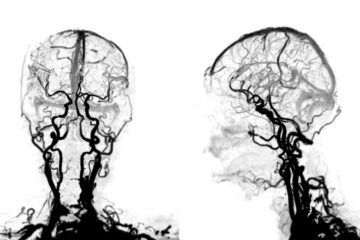

Radiologiniai tyrimai

Radiologiniai tyrimai padeda aptikti navikus ir kitas galimas pakitimo vietas:

- Kompiuterinė tomografija (KT)

- Magnetinio rezonanso tomografija (MRT)

- Bario tyrimas, kurio metu išgeriamas skystis, leidžiantis aiškiau matyti skrandžio gleivinę rentgeno nuotraukose

- Pozitronų emisijos tomografija (PET) – leidžia nustatyti, ar vėžys išplitęs po visą kūną